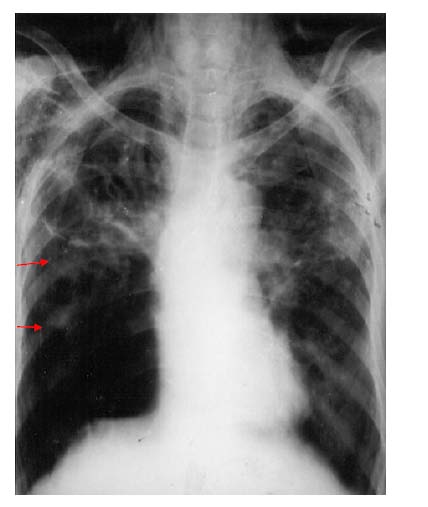

Notice the pneumothorax at the right lower zone. Though it is a small pneumothorax it is clearly visible -Hyperlucency without lung markings laterally and margin of the collapsed lung covered by the visceral pleura medially. Note the blunted costophrenic angle. What caused this pneumothorax?

Look at the lower zone on the other side (red arrow) -you will observe a hyperlucent circular area but no pneumothorax-a Bulla, which can sometimes mimic a cavity or a pneumothorax. A similar bulla on the right side must have resulted in the Pneumothorax.